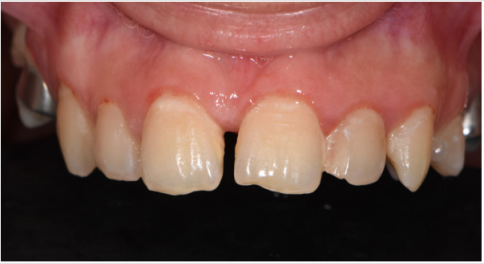

At the end of the expansion period, the anterior and posterior crossbite was solved and in the vertical plane, the lateral open bite had clearly improved. The upper jaw from the occlusal view has visible changes in its transversal dimension and space was gained, proof being also the diastemas that appeared between all teeth not only the median one. After the expansion, the patient will wear edgewise appliances for correction of the crowding, the interincisal midlines and for detailing and stabilizing the occlusion (Figures 9-11).